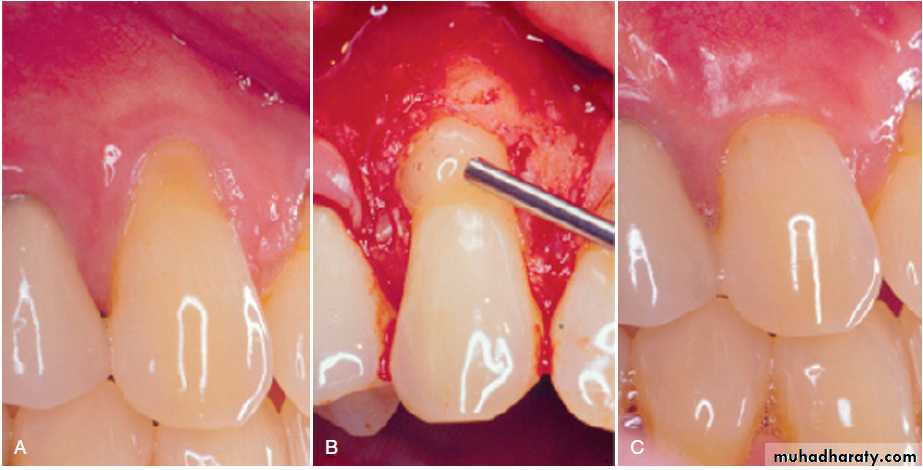

High frenum attachments. A, Frenum between maxillary central incisors. B, Frenum attached to facial surface of maxillary lateral incisors. C, Frenum attached to facial surface of mandibular incisor. D, Frenum attached to facial surface of an incisor.